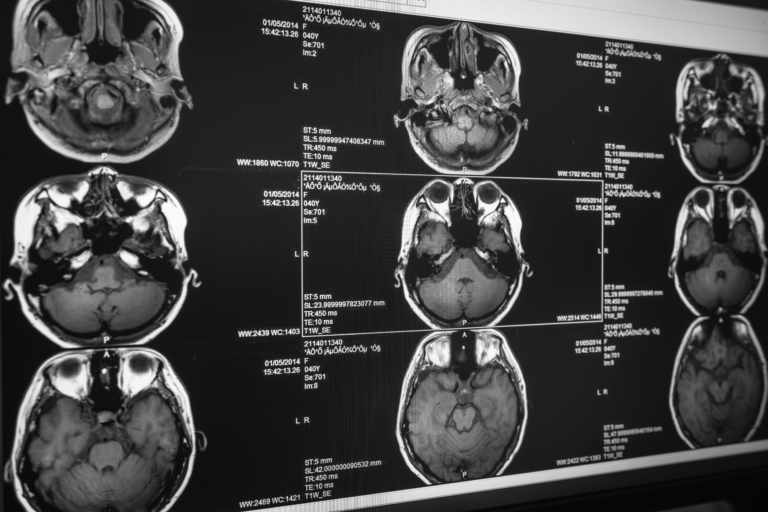

Wie werden vestibuläre Erkrankungen diagnostiziert?

Ärzte nutzen die Informationen aus der persönlichen Krankengeschichte und die Befunde der körperlichen Untersuchung als Grundlage, um diagnostische Tests anzuordnen, womit sie die Funktion des vestibulären Systems untersuchen und alternative Ursachen der Symptome ausschließen.